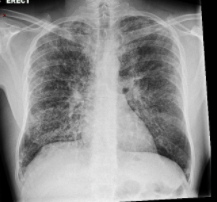

A 40 year old man with a background history of alcohol excess was admitted to hospital with 3 month history of significant weight loss, non productive cough and shortness of breath. He travels frequently with his work.

Chest auscultation only revealed a few basal crepititions, saturations were 92% on air. But he desaturates to 80% on minimal exertion.

Bloods -WCC 3.9, Platelets 100, CRP 23.

What is the most likely diagnosis?

pneumocystis jiroveci pneumonia

What is the underlying diagnosis?

HIV

What is the likely CD 4 Count?

<200